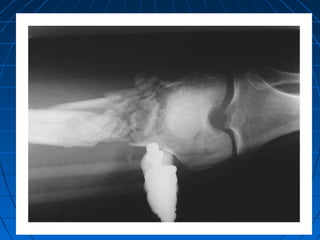

Extremity InjuryExtremity Injury Traumatic amputation, fractures, crush injuries,Traumatic amputation, fractures, crush injuries,

Blast Extremity InjuriesBlast Extremity Injuries

Traumatic amputationTraumatic amputation

Blast Extremity InjuriesBlastExtremity Injuries Traumatic amputationTraumatic amputation Initial ManagementInitial Management ••Even when blast victims have small entrance wounds,Even when blast victims have small entrance wounds, surgeons should maintain a low threshold for performingsurgeons should maintain a low threshold for performing thorough debridementthorough debridement ••All open fractures are considered contaminated andAll open fractures are considered contaminated and should receive early antibiotic treatment (first generationshould receive early antibiotic treatment (first generation cephalosporin and/or aminoglycoside, extended spectrumcephalosporin and/or aminoglycoside, extended spectrum penicillinpenicillin(( ••Obviously contaminated wounds should be irrigated withObviously contaminated wounds should be irrigated with sterile saline and dressed with iodophore (Betadine)-sterile saline and dressed with iodophore (Betadine)- soaked sponges; once dressed, re-exposure should waitsoaked sponges; once dressed, re-exposure should wait until operative explorationuntil operative exploration